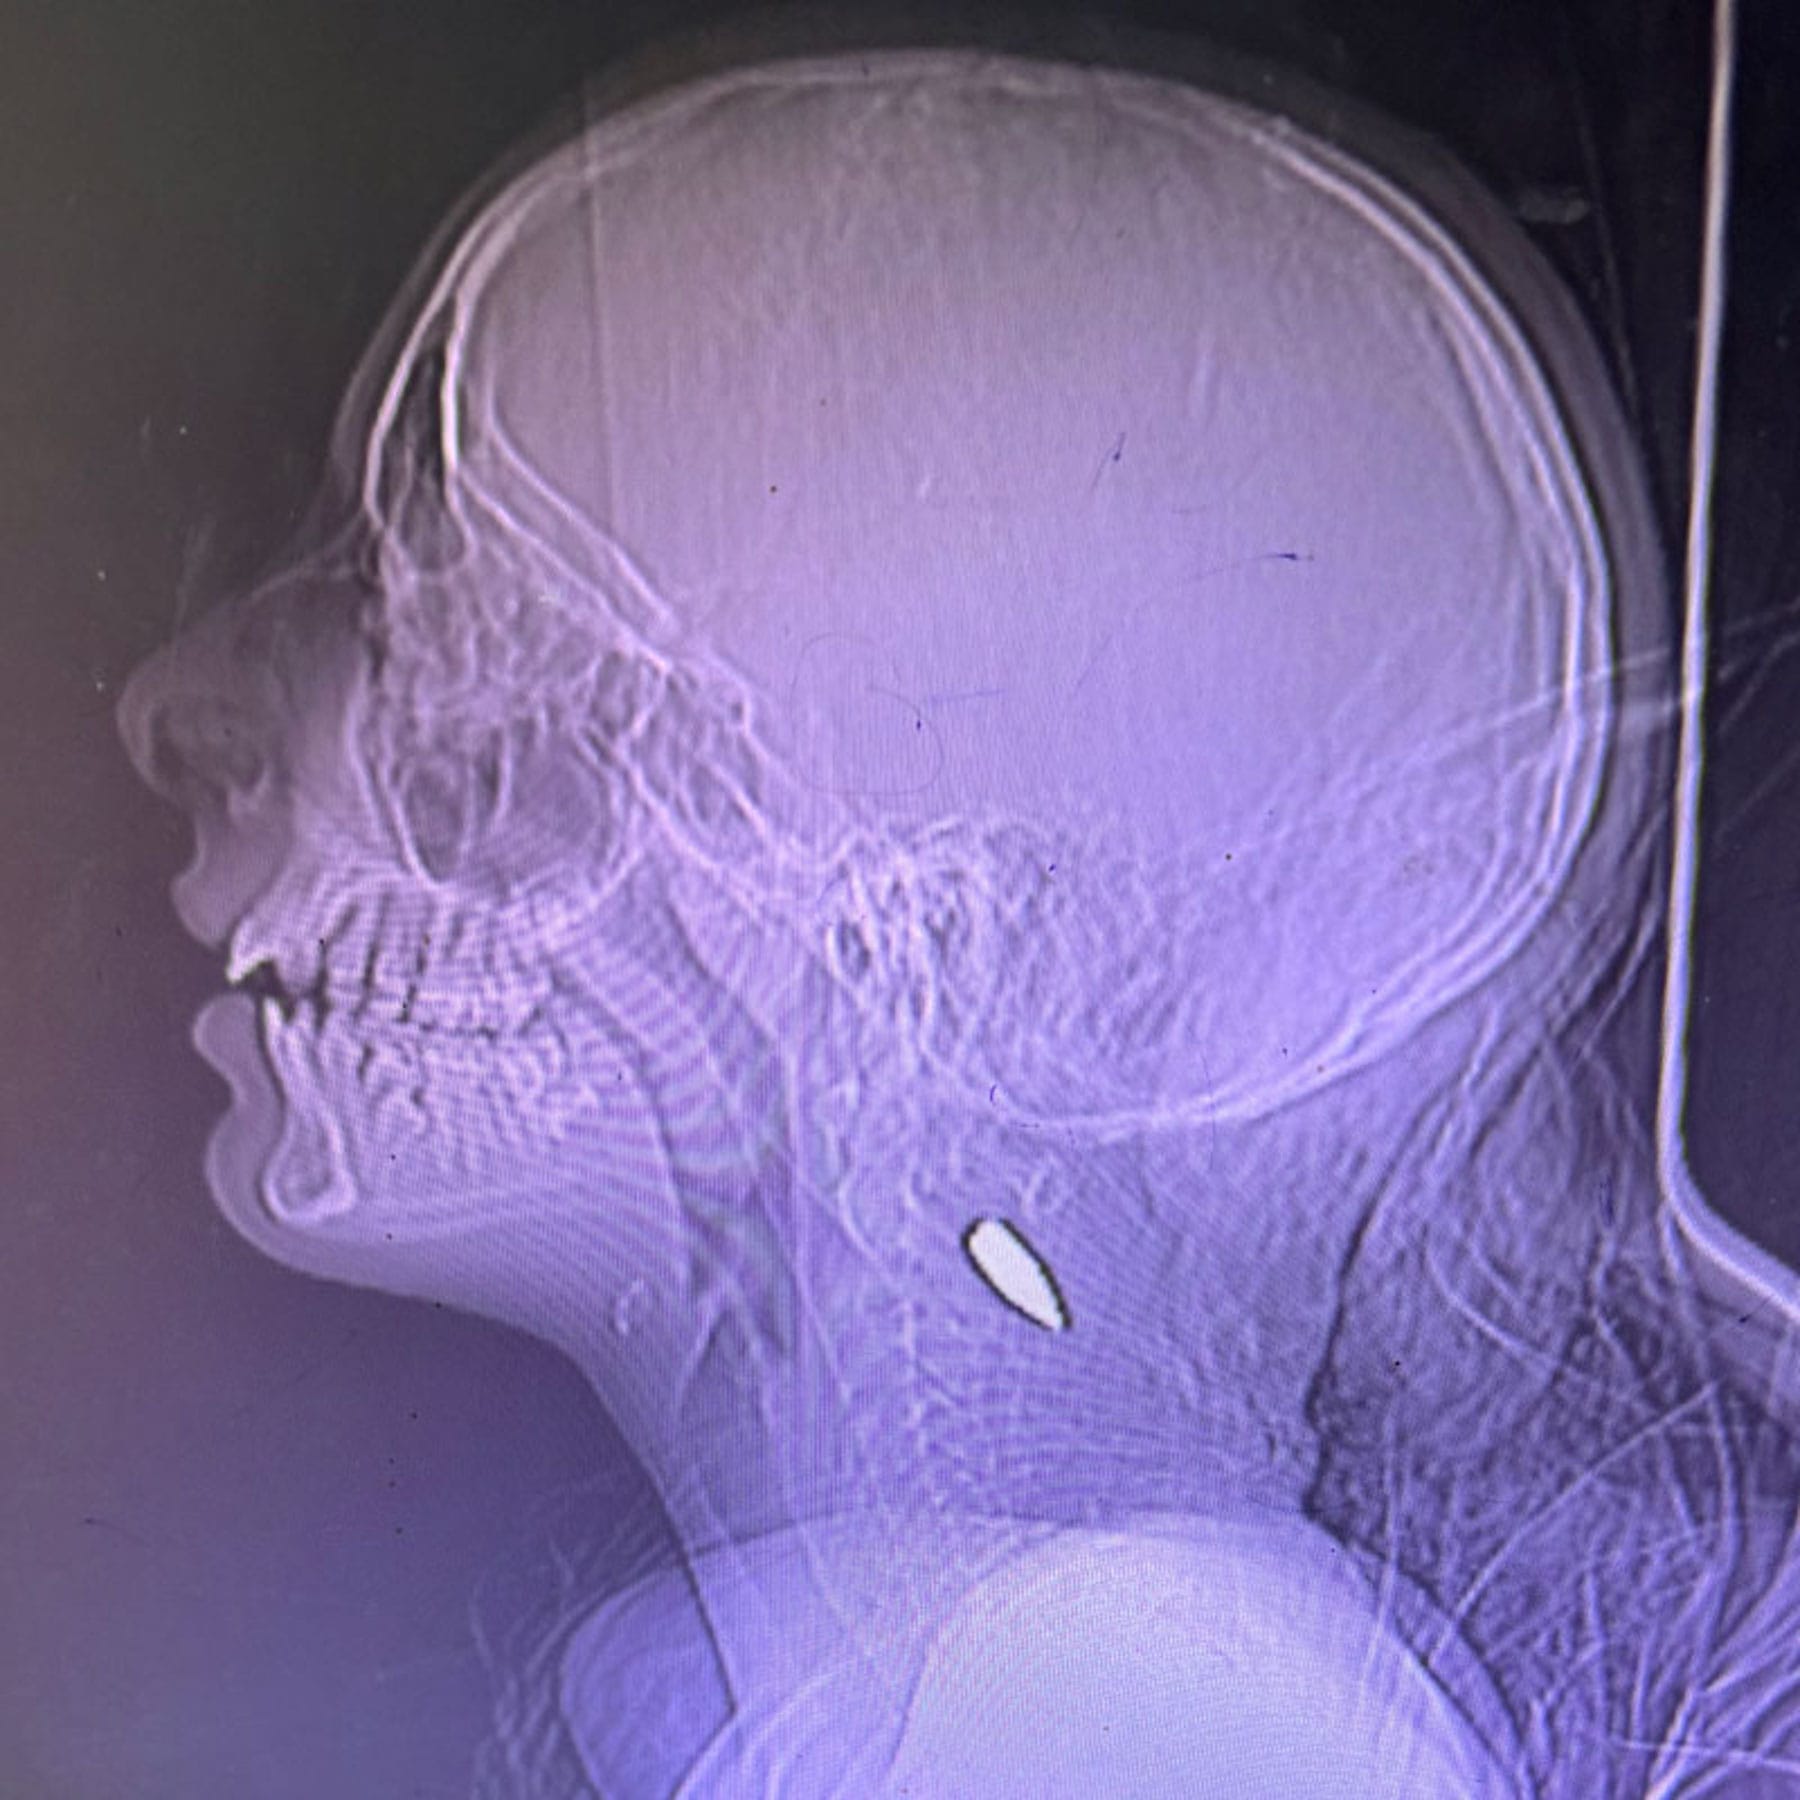

“One night in the emergency department, over the course of four hours, I saw six children between the ages of 5 and 12, all with single gunshot wounds to the skull,” Dr Mohamad Rassoul Abu-Nuwar, a surgeon from Pittsburgh, said.

23-year-old paramedic Rania Afaneh said shetreated a child who had been shot in the jaw. The child was fully conscious but couldn’t stop choking on his own blood, she said.